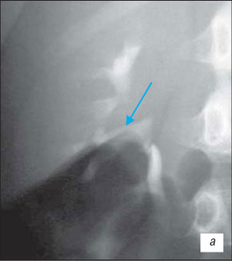

Висхідна цистографія

На даній рентгенограмі спостерігаємо активно-пасивний міхурово-сечовий рефлюкс зліва 4 ступені. Виражена дилатація чашечко-мисочкової системи, деформація чашок.

а – у фазі максимального наповнення сечового міхура, пасивний рефлекс; б – у фазі сечовипускання, активний рефлекс.